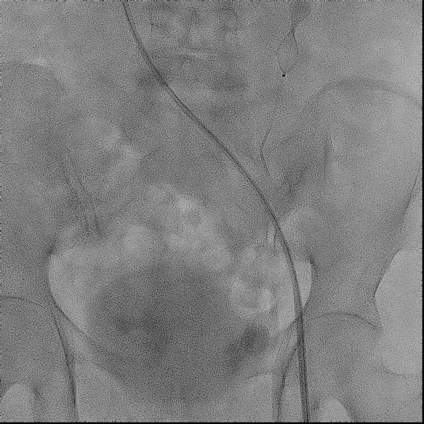

手术过程(一):

右股静脉穿刺,交换8 F-90 cm长鞘导入A3段,造影见A3段远端显影良好,中段动静脉瘘高速血流,可见“瘤槽”显影。

图片图片